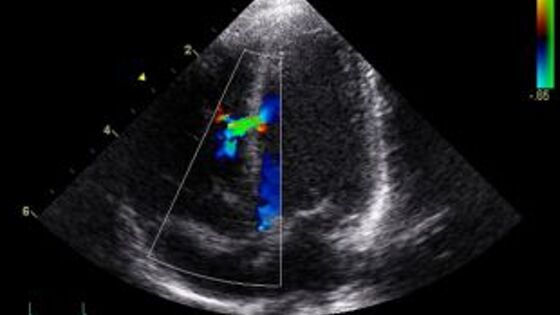

Посетивший Самарский областной клинический кардиологический диспансер заведующий отделением хирургического лечения сложных нарушений ритма сердца и электрокардиостимуляции Российского научного центра хирургии имени академика Петровского Алексей Цыганов поделился с самарскими коллегами инновационным опытом лечения сложных сердечных заболеваний, сообщает региональное правительство. Врач отделения хирургического лечения сложных нарушений ритма сердца и электрокардиостимуляции Самарского областного клинического кардиологического диспансера Степан Поляков, внук известного самарского кардиохирурга Виктора Полякова совместно с московским специалистом провели операцию по новой методике с применением хирургической радиочастотной абляции участка аритмии. Процедура выполняется малоинвазивным способом, без разрезов через небольшие проколы на коже диаметром всего два миллиметра. Врачи проводят абляцию аритмии, воздействуя на нее радиочастотной энергией с помощью специального электрода. В ход идет самое передовое оборудование. За ходом операции хирург следит на мониторе, где отображается сердце в формате 3D, и виден вектор движения электрода. Эта информация выделена соответствующим цветом - от светлого до темно-красного. Ранее в областном кардиодиспансере операции по лечению тахиаритмии выполняли с использованием реагента. Новая методика не подвергает пациента опасному облучению и риск осложнений снижается на 15-20%. Уже на следующий день после операциипациент может выходить на работу. В этом году в кардиодиспансере планируют выполнить 180 операций с использованием новой методики в рамках оказания высокотехнологичной медицинской помощи.